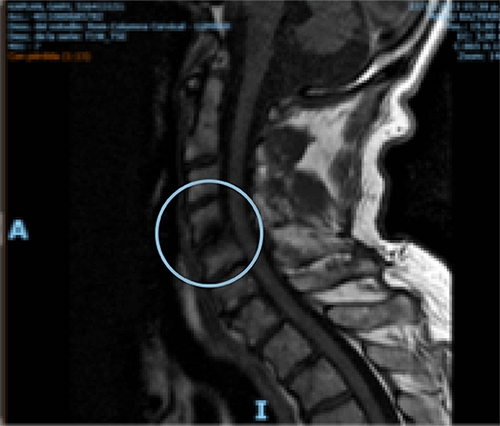

Comparative MRI of cervical spine pre- and one-year post-treatment in a 70-year-old man diagnosed with osteoarthritis of the cervical spine. The red arrow shows the remodeling of the affected disc.

BEFORE